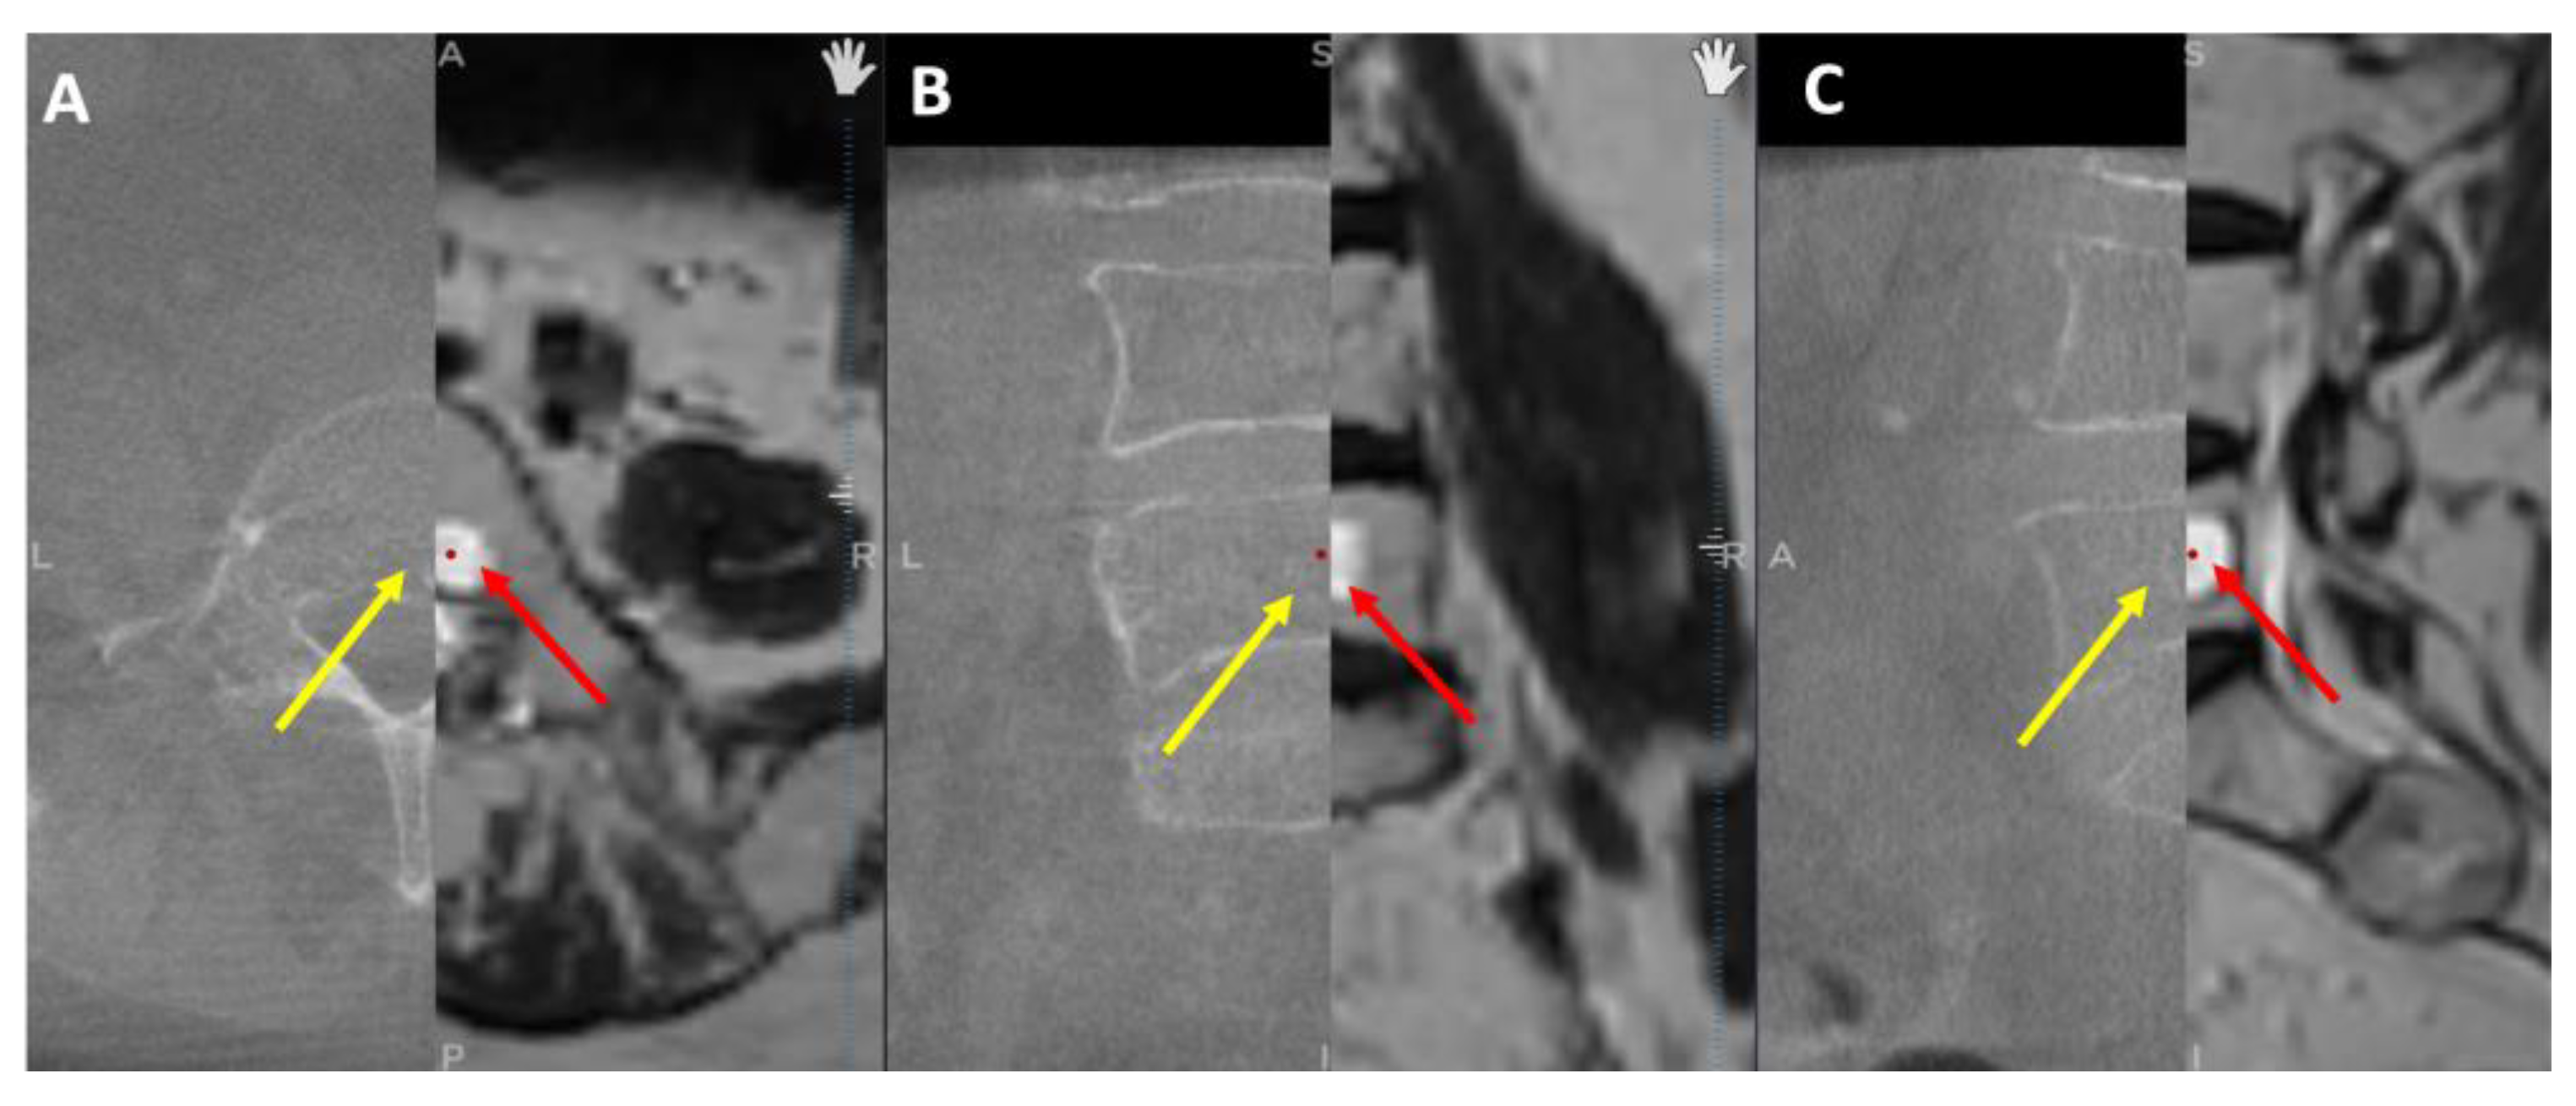

Initially, the entry point is determined through the O-arm scan (Figure 1). Next, the target point for sampling is set using an MRI scan (Figure 2). Afterward, the surgical plan for the needle biopsy is progressed by utilizing the instrument projection function.

Figure 2. MRI scan, the yellow projection line displays the targeted biopsy site for the needle biopsy procedure, with A) Axial view, B) Coronal view, and C) Sagittal view.